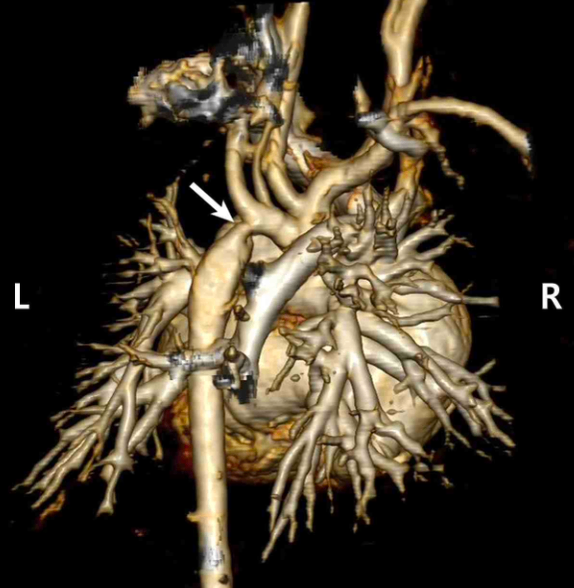

생후 7일 남아가 2일 전부터 호흡곤란과 소변량이 줄어 병원에 왔다. 임신나이 39주 5일, 출생체중 3,300 g, 질분만으로 태어났다. 출생 시 특이 문제는 없었다. 혈압은 오른팔 60/35 mmHg, 왼다리 45/25 mmHg이다. 심박 160회/분, 호흡 65회/분, 체온 36.8°C이다. 복장뼈 왼쪽 가장자리에서 2/6도의 수축기 심잡음이 들리며, 넓적다리맥박이 약하게 만져진다. 심장 컴퓨터단층촬영 사진이다. 진단은?

CT: Focal aortic narrowing distal to aortic arch

Imp: 대동맥 축착(coarctation of aorta, CoA)

상하지 혈압이 다르고 흉골좌연 수축기 심잡음이 청진되며, CT에서 하행 대동맥의 축착이 확인되므로 CoA로 진단한다.

• 실제로 심장 컴퓨터단층촬영 사진에서 하행 대동맥의 축착이 확인되므로 대동맥 축착(CoA)으로 진단한다.